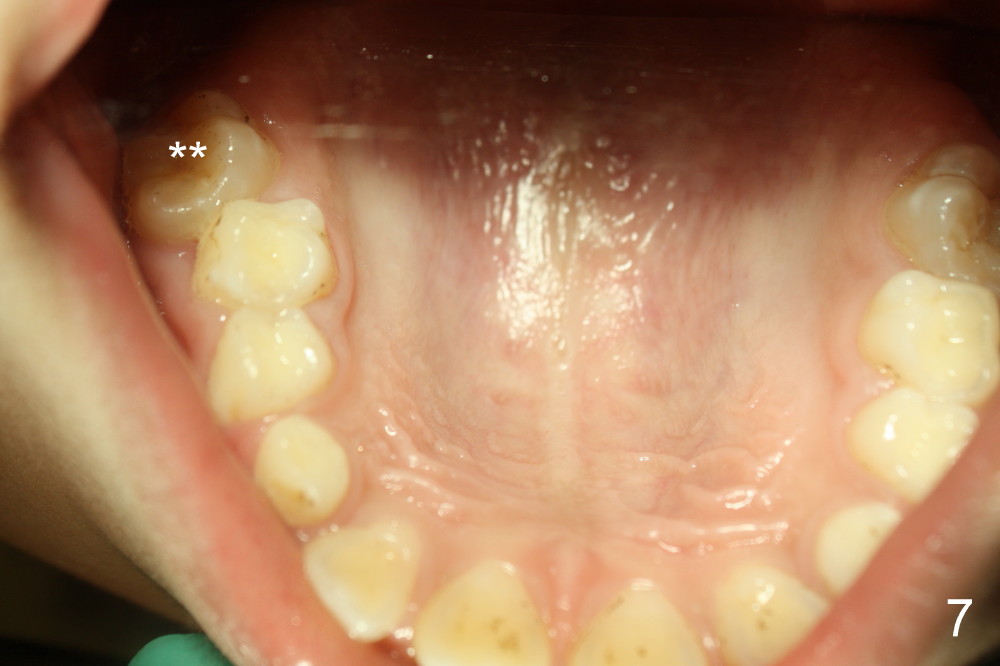

It appears that the chin deviates to the left (Fig.1). The lower dental midline also deviates (Fig.2,4). Profile shows possible bimaxillary protrusion (Fig.3). There is cross bite (deep overjet?) on the right side of the first permanent molars (Fig.5 mirror image), whereas the left posteriors apparently present edge-to-edge occlusion (Fig.6). Fig.7,8 are mirror views of the upper and lower arches, respectively. Panoramic X-ray demonstrates elongation of the right condyle (Fig.9). The right ramus appears to be longer than the left.